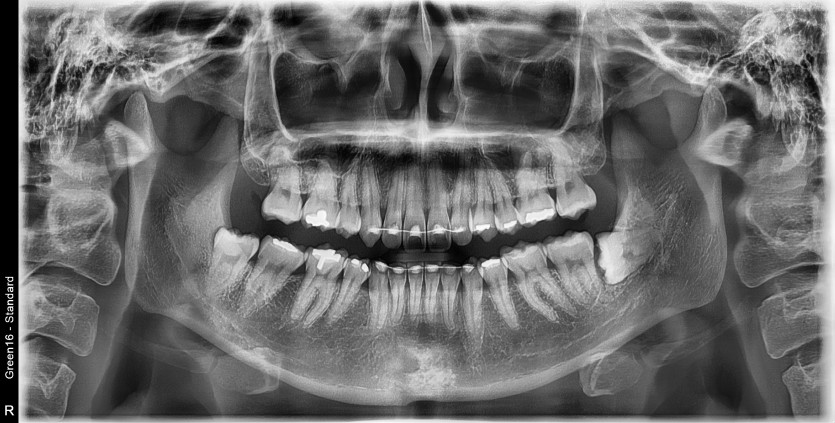

#48 사랑니 발치

구강외과 전문의가 당일 발치했습니다.